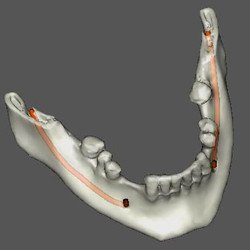

INTERPRETAÇÃO DA TOMOGRAFIA

Na apresentação básica, a reconstrução do exame tomográfico aparece como fatias de imagens

nos três planos: coronal, axial e sagital.

O radiologista “navega” por estas imagens, analisando toda a aquisição e com o auxílio de ferramentas ele monta e escolhe as imagens que irão compor o filme.

Nos softwares há ferramentas que permitem a reconstrução e a obtenção de novos cortes que mostram imagens de uso pontual na odontologia como os cortes transversais e longitudinais.

Os cortes transversais são cortes perpendiculares ao arco da maxila e mandíbula.

Na reconstrução panorâmica aparece uma régua no limite inferior que serve de localização para os cortes transversais.

Os cortes longitudinais são cortes no sentido vestíbulo lingual ou palatino, perpendiculares a uma reta traçada sobre o dente ou a área em questão.

1- A reconstrução panorâmica nada mais é que a representação em forma de panorâmica a partir de um arco criado sobre o rebordo, dessa forma, estruturas fora desses limites de reconstrução não aparecerão, diferente da radiografia panorâmica, onde estruturas “fora do foco” aparecem superpostas e por vezes borradas.

2- Nos cortes sagitais o perfil não muda para lado direito e esquerdo, os cortes são seqüenciais.

3- Por vezes utilizaremos a apresentação das imagens em MIP (Projeção de Intensidade Máxima) que dá o aspecto 3D de crânio seco.